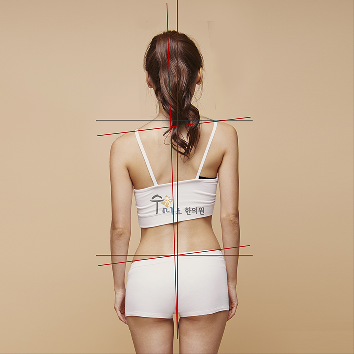

또 제자리걸음을 이용한 자가진단법도 있는데요. 눈을 감고 팔을 크게 흔들면서 다리를 높게 올리는 제자리걸음을 50회 반복합니다. 그리고 눈을 뜨고 위치를 확인했을 때, 처음 위치 그대로라면 굉장히 바른 체형이라고 볼 수 있습니다. 하지만 처음 있는 곳에서 벗어났다면, 그 방향으로 골반이 틀어진 것인데요.

골반이 앞으로 기울어진 전향형, 뒤로 기울어진 후향형과 왼쪽 골반과 어깨가 처져있는 좌형, 반대인 우형으로 나눌 수 있습니다.

추가로 몸의 방향이 처음(자신이 보고 있던 방향)에서 왼쪽으로 돌아갔다면 좌향형, 반대면 우향형으로 나눌 수 있는데요. 골반이 왼쪽으로 돌아가 있는 상태인 좌향형은 상체가 왼쪽으로 돌아가 있고 오른쪽 어깨가 앞으로 나와 있으며, 우향형은 그 반대라고 합니다.